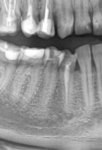

Сап двач, вот что делать бедному студенту, который переживает за свои зубы? Конечно создать тред и спросить местных стоматологов. Стрелочкой я указал проблемный зуб. Сут такая: у меня там как бы трещина и получается так, что пропасть (хз как сказать) до десны доходит и там застревает еда, которую я вытаскиваю зубочисткой. Чем мне обернется отказ от лечения? Зуб не болит.